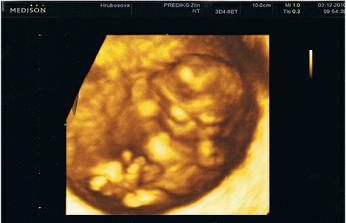

Naše miminko

Super fotecka z ultrazvuku;)Gratuluji k miminku

to jsou opravdu krásné vydařené fotky z UTZ 🙂